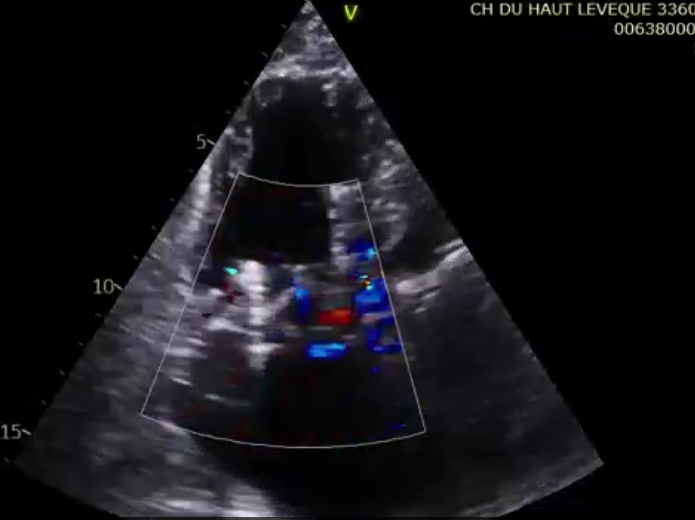

術(shù)前超聲提示大量三尖瓣反流